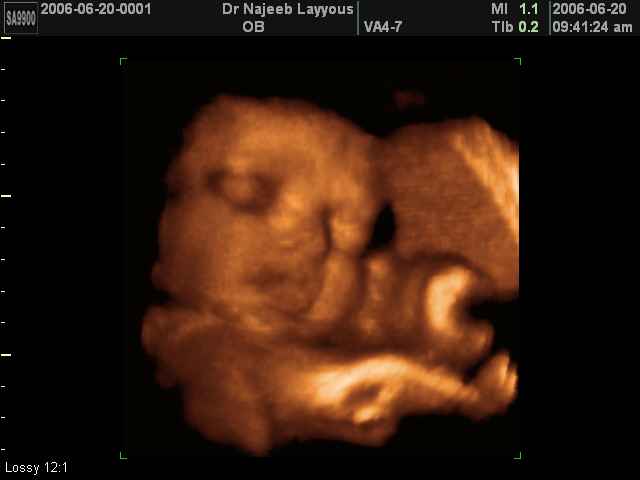

- Fetal Behavior Ultrasound Photos

Ultrasound Photos in 3D showing Fetal Behavior Inside the uterus | Dr N Layyous